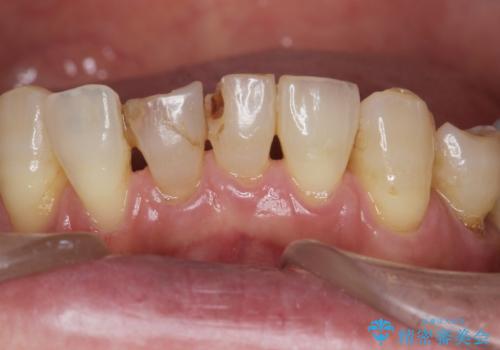

- 下の前歯が欠けてぐらぐらすることを主訴に来院された患者様です。

以前行った奥歯の治療により下顎前歯の動揺は改善傾向にあり顕著ではなかったのですが、欠けて黒くなっていることと少しの動揺が気になるとのことでした。

元気なうちに治療しておきたいという患者様の強いご希望により、下顎前歯の連結補綴と欠けている小臼歯の補綴治療を行いました。